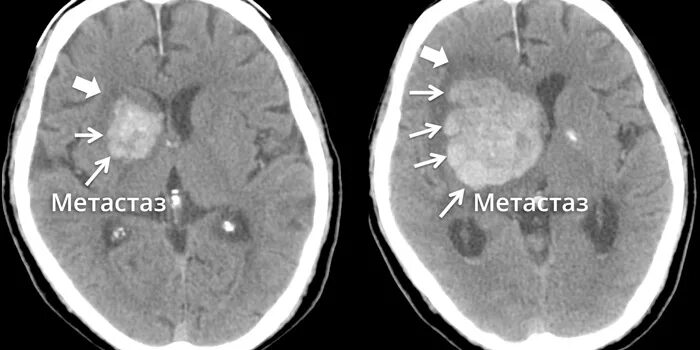

Отек мозга метастазы